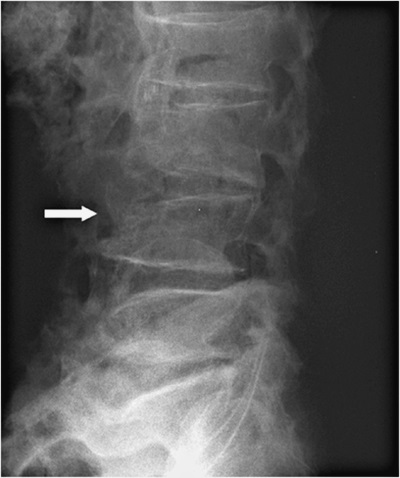

На 3-й день после состоявшегося осмотра участковым врачом выполнена рентгенограмма поясничного отдела позвоночника (см. рис. 1).

Заключение в поликлинике: остеохондроз поясничного отдела позвоночника, остеофиты всех поясничных позвонков. Компрессионные изменения L4.

Рисунок 1. Рентгенограмма поясничного отдела позвоночника